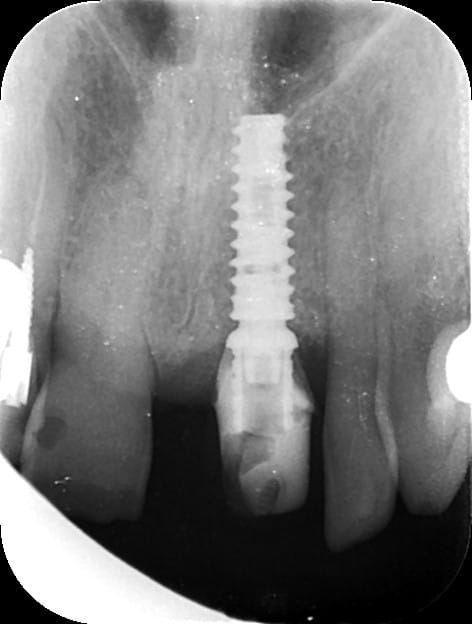

et pour le fun, ce que j'ai fait ce matin en 15min là aussi...

la patiente ne voulais pas faire de sinus lift car elle avait eu pas mal de pb de ce côté là...

donc, j'ai posé l'implant à raz le long du plancher sinusien

et bien, je souhaite bien du plaisir à qui doit poser un implant de la sorte à main levée en prenant à la fois en compte le sinus et l'émergence du col de l'implant pour ne pas avoir de pb pour faire la prothèse...

à part y aller millimètre par millimètre et prendre des radios à chaque fois....

P.S: j'ai quand même vérifié après l'insertion finale que je pouvais connecter un transfert...bilan, aucun problème!

Capture1 bzketg - Eugenol

Sinus zbjhxn - Eugenol

et la 6 c'est bon ? :)))))))

P.S: pour goupil, oui la 16 n'est pas dans une forme olympique...on peut en dire autant pour la 14...

seulement voilà: ce cas m'est adressé, j'ai longuement parlé avec mon confrère et la patiente des différentes options et c'est celle qui a été retenue...

pour info quand même, ces dents sont totalement asymptomatiques et n'ont aucune mobilité...